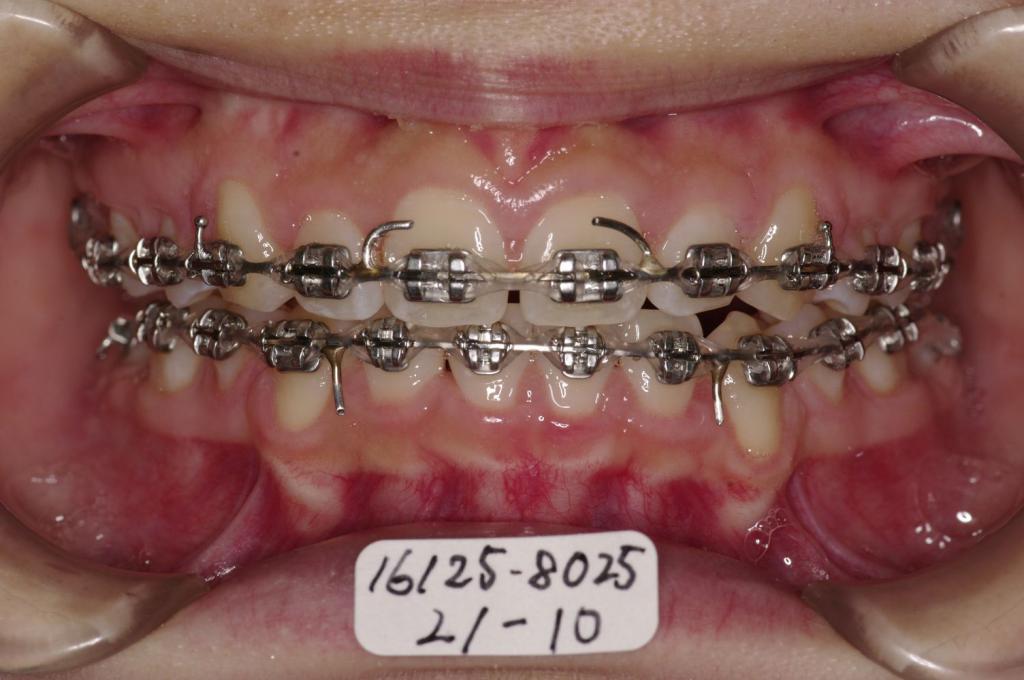

装置写真

治療前

前歯、出っ歯・開咬の矯正治療前口内写真NO.1093

治療後

前歯、出っ歯・開咬の矯正治療後口内写真NO.1093